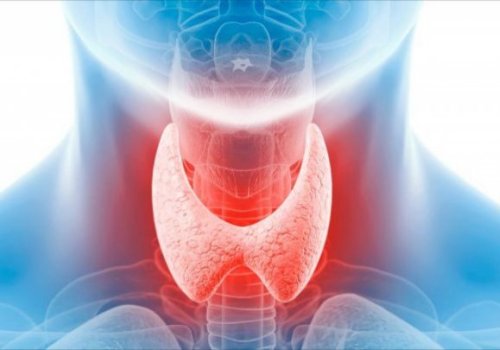

Qalxanabənzər vəz ilə əlaqə

Hormonal balansda qalxanabənzər vəz (tiroid) mühüm rol oynayır. Bu vəz bədənin maddələr mübadiləsini tənzimləyən hormonlar ifraz edir.

Əgər qalxanabənzər vəz düzgün işləməzsə:

Maddələr mübadiləsi zəifləyir və ya sürətlənir

Enerji səviyyəsi düşür

Saç tökülməsi artır

Əhval pozuntuları yaranır

Xüsusilə qadınlarda tiroid problemləri daha çox rast gəlinir və çox vaxt hormonal disbalansın əsas səbəblərindən biri olur.